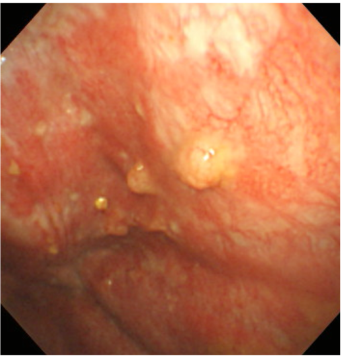

T1a期(IMIG分類)の胸膜中皮腫の胸腔鏡所見

壁側胸膜に顆粒状の腫瘍を認める。